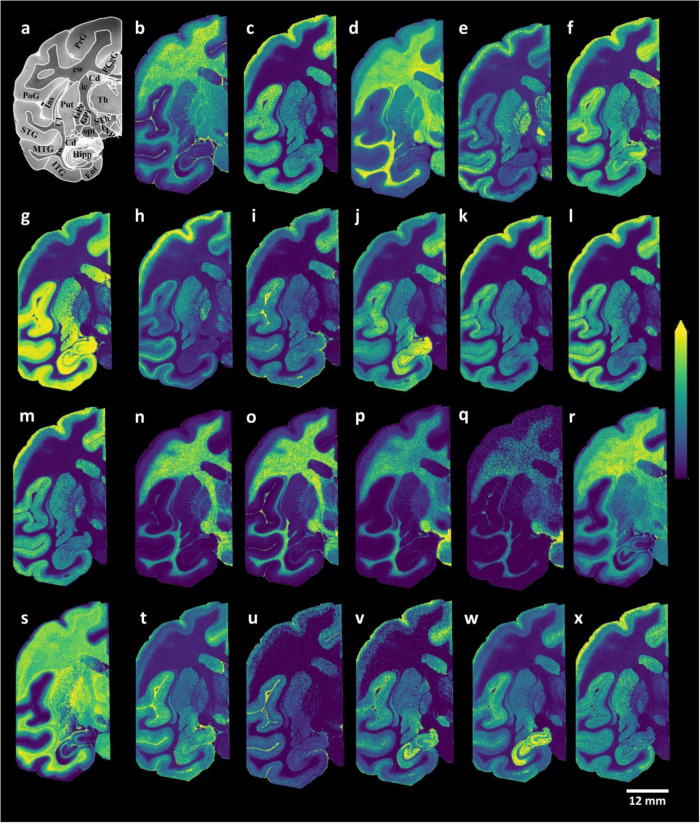

Distributions of glycerophospholipids and sphingolipids within control brain tissue sections

Animal models have provided several fundamental insights into brain aging and neurodegeneration-related brain function alterations33,34. The remarkable similarities between humans and macaque monkeys in terms of behavioral capacities, sensory processing abilities, and brain architecture have led to macaque brains becoming the predominant non-human primate model system in brain aging and neurodegeneration research33,34. Therefore, it is critical to analyze macaque brain tissue sections with MALDI-MSI to understand the brain region-specific roles of lipids and provide a basis for further research. We initially focused on the lipid species that could be detected and imaged in the control macaque brain tissue sections based on the analysis of both control and MPTP-treated macaque brain tissue sections. The data were obtained from dual polarity MALDI-MSI analyses of coronal sections from one hemisphere of non-human primate brains (150 µm lateral resolution; Fig. 1). Several discrete brain regions, including the postcentral gyrus (PoG), the precentral gyrus (PrG), the posterior cingulate gyrus (PCgG), the subthalamic nucleus (STh), the superior temporal gyrus (STG), the middle temporal gyrus (MTG), the inferior temporal gyrus (ITG), the entorhinal area (Ent), the hippocampus (Hipp), the caudate nucleus (Cd), the insula (Ins), the claustrum (Cl), the putamen (Put), the globus pallidus externa (GPe), the globus pallidus interna (GPi), the optic tract (opt), the thalamus (Th), the internal capsule (ic), the temporal white matter (tw), cerebral white matter (cw), and substantia nigra pars reticulata (SNR) were chosen for the analysis (see Fig. 1a). Several glycerophospholipid species, phosphatidylserine (PS) (Fig. 1b, c), phosphatidylcholines (PC) (Fig. 1d, e), phosphatidylinositol (PI) (Fig. 1f–h), phosphatidylethanolamine (PE) (Fig. 1i–m), and sphingolipid species, includingsphingomyelins (SM) (Fig. 1n, o), hexosylceramides (HexCer) (Fig. 1p, q), sulphated hexosylceramides (SHexCer) (Fig. 1r, s), ceramide phosphates (CerP) (Fig. 1t), monosialogangliosides (GM) (Fig. 1u–w) and disialogangliosides (GD) (Fig. 1x) were visualized within numerous brain regions, including temporal and cerebral cortical areas, along with motor-related brain areas (e.g., the caudate and putamen, the precentral gyrus, the internal and external segments of the globus pallidus, and substantia nigra pars reticulate) (Fig. 1a). Interestingly, PS (36:1) and PC (36:1) were primarily localized to white matter regions (Fig. 1b, d), while longer-chain and polyunsaturated fatty acid-containing PS (40:6) and PC (40:6) species were localized to the grey matter areas (Fig. 1c, f). The PI species PI (36:4), PI (38:4), PI (40:6), PE species PE-NMe2 (32:0), PE (38:4), PE (P-40:6), GM and GD species GM3 (36:1), GM2 (36:1), GM1 (36:1), GD1 (36:1), and CerP species CerP (36:1) were predominantly localized within grey matter areas in the coronal macaque brain tissue sections (Fig. 1). As expected, myelin-associated lipid species, including SM species SM(d42:2), SM(d42:1), HexCer species HexCer(d42:2), HexCer(d42:1), and SHexCer species SHexCer (d42:2), SHexCer (d42:1), were localized to the white matter regions (Fig. 1). Subsequent staining of the tissue sections analyzed with dual polarity MALDI-MSI with luxol fast blue (Fig. 2a) revealed that myelin lipid species, including SHexCer (d42:2) (Fig. 2b), HexCer(d42:2) (Fig. 2c), and SM(d42:2) (Fig. 2d), were primarily distributed to myelin-rich brain areas, including the cerebral and temporal white matter areas, the thalamus, the optical tract, and the internal capsule, within coronal macaque brain tissue sections.

Fig. 1. MALDI-MSI images of glycerophospholipid and sphingolipid species.

a Bright-field image of a macaque brain tissue section with annotated brain regions. Dual polarity MALDI-MSI of the same tissue section (shown in a) reveals the ion images of b [PS (36:1)-H]−, c [PS (40:6)-H]−, d [PC(36:1) + K]+, e [PC(40:6) + K]+, f [PI (36:4)-H]−, g [PI (38:4)-H]−, h [PI (40:6)-H]−, i [PE-NMe2 (32:0)-H]−, j [PE (38:4)-H]−, k [PE (38:6)-H]−]−, l [PE (40:6)-H]−, m [PE (P-40:6)-H]−, n [SM(d42:2) + H]+, o [SM(d42:1) + K]+, p [HexCer(d42:2)+Na]+, q [HexCer(d42:1)+Na]+, r [SHexCer (d41:1)-H]−, s [SHexCer (d43:2)-H]−, t [CerP (36:1)-H]−, u [GM3 (36:1)-H]−, v [GM2 (36:1)-H]−, w [GM1 (36:1)-H]−, x [GD1 (36:1)+Na-2H]− in a coronal control macaque brain tissue section. All ion distribution images are scaled to the maximum intensity of each individual ion. PoG postcentral gyrus, PrG precentral gyrus, PCgG posterior cingulate gyrus, STh subthalamic nucleus, STG superior temporal gyrus, MTG middle temporal gyrus, ITG inferior temporal gyrus, Ent entorhinal area, Hipp hippocampus, Cd caudate nucleus, Ins insula, Cl claustrum, Put putamen, GPe/GPi globus pallidus externa/interna, opt optic tract, Th thalamus, ic internal capsule, tw temporal white matter, cw cerebral white matter, SNR substantia nigra pars reticulata. Lateral resolution is 150 µm and all of the ion images were RMS-normalized. The coronal section was obtained at −6 mm relative to the anterior commissure.